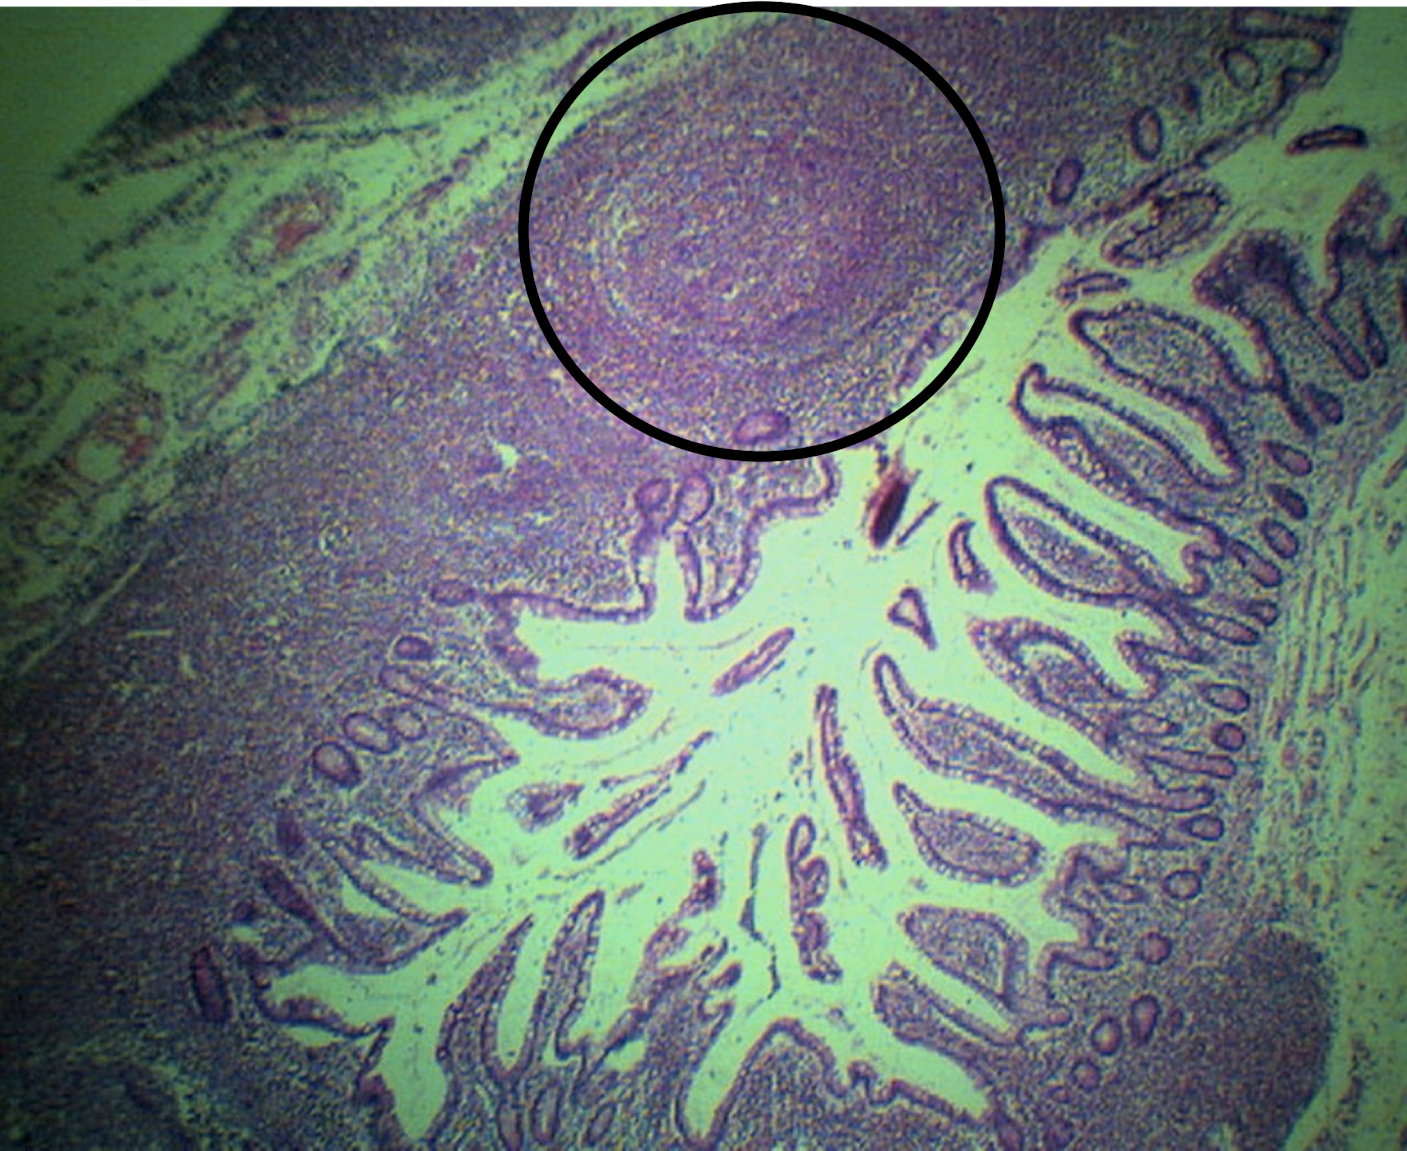

ILEUM

peyer’s patches

lymphoid nodular aggregates

Identify the structure and its characteristic feature

A: villi

B: peyer’s patch

C: submucosa

Identify the structure

A: muscularis mucosa

B: lamina propria

C: lining epithelium

D: peyer’s patch

E: crypts or lieberkuhn (intestinal glands)

F: submucosa